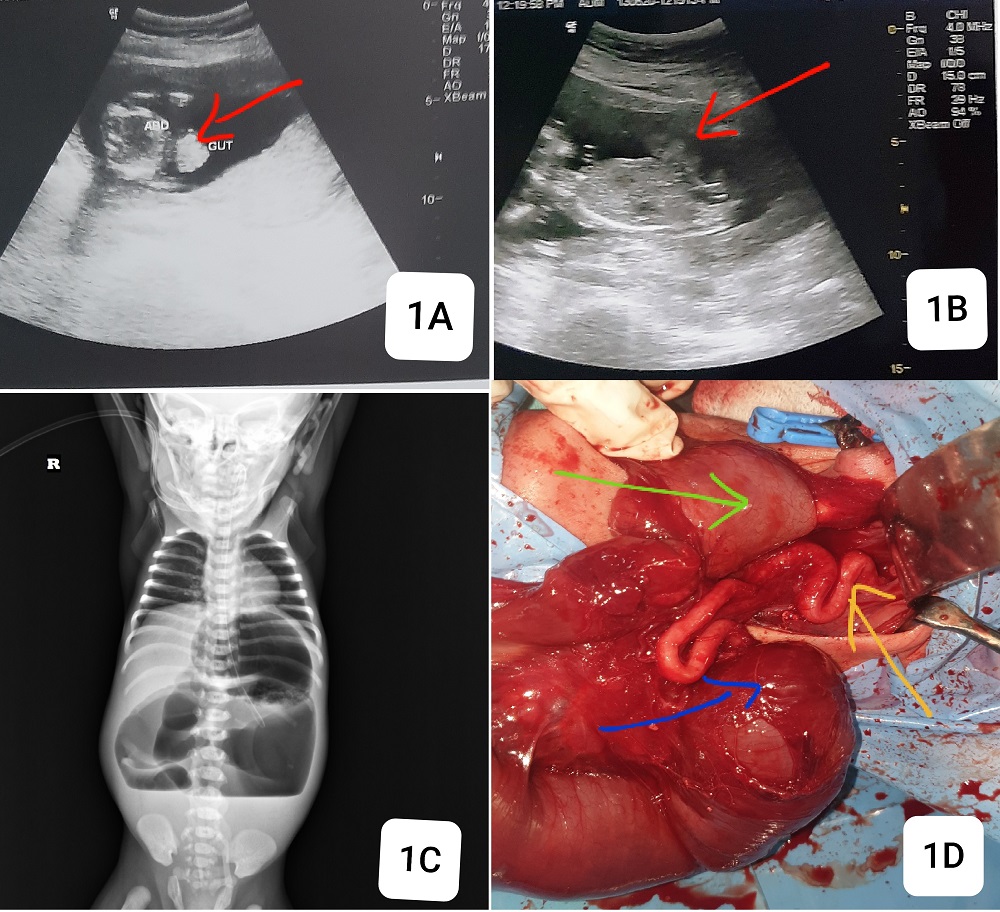

A 2-day-old female neonate was brought to our institute with bilious vomiting. On clinical examination, there was abdominal distension with visible palpable few loops, and a normal umbilicus. She was born to a 20-year-old primigravida. There was a history of antenatal diagnosis of gastroschisis. On analysis of her antenatal scans, the first obstetric scan at 16 weeks of gestation showed bowel herniation through an abdominal wall defect without any covering sac (Fig.1A,1B). Fetal anomaly scan at 20 weeks gestation was indifferent, but the 26-week scan showed additional findings of early-onset fetal growth restriction, normal amniotic fluid volume, and three vessels in the cord. Mother had labor pains at 32 weeks, and spontaneously delivered a female premature baby of 1.95kg at home. At birth, there was no visible abdominal wall defect, but the baby developed bilious vomiting and feeding intolerance on day one and referred to us by the pediatrician on day 2. Plain X-ray abdomen showed markedly dilated small bowel loops with air-fluid levels suggestive of obstruction (Fig.1C). The baby was resuscitated and optimized. On exploratory laparotomy, there was about 25 cm of remaining markedly dilated small bowel from gastro-duodenal junction to jejunal atresia (Type 1) and colon was about 15 cm. Most of the midgut structures including part of the jejunum, ileum, cecum, appendix, and most of the colon vanished (Fig.1D). A jejunostomy and distal colonic mucus fistula were formed after discussion of findings with the parents. On postoperative day 2, the stoma started functioning and feeding was started. After counseling, the parents choose palliative care at home. The patient died on the 25th day after surgery at home without any hospital visit.

1A and 1B) antenatal scans at 16 and 20 weeks, with red arrow showing gastroschisis. 1C) plain abdominal erect X-ray with dilated small bowel and 3 air-fluid levels. 1D) intraoperative finding of dilated stomach (green arrow), jejunal atresia (blue arrow), and short length atretic colon (yellow arrow).